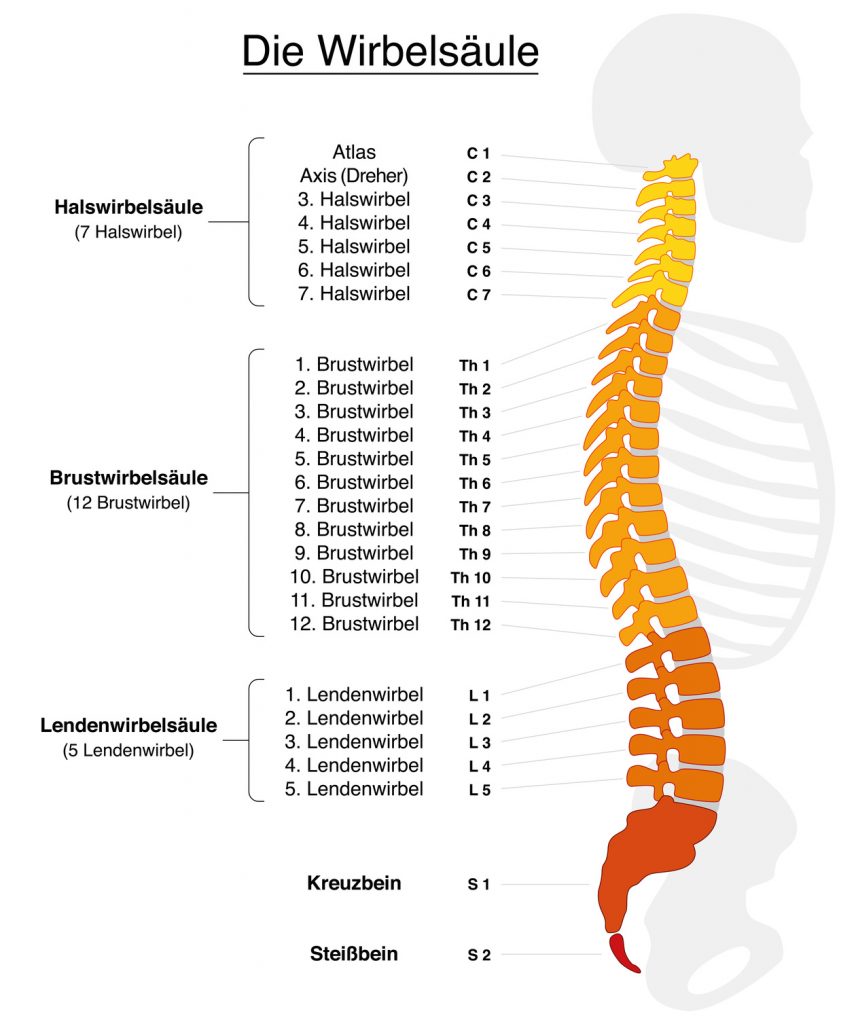

2025 07 10

Bilder können urheberrechtlich geschützt sein Mehr Informationen